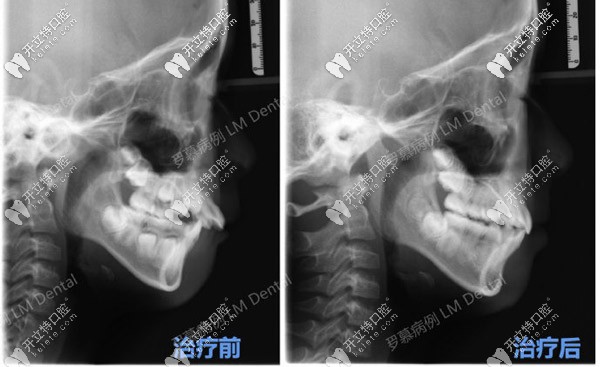

CT可以明顯看到羅慕干預(yù)后的效果▲

治療前后的數(shù)據(jù)對(duì)比▲